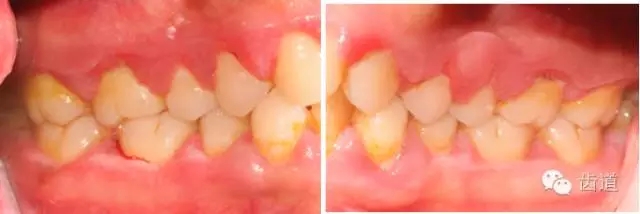

1、口腔衛(wèi)生狀況及局部刺激物(牙菌斑、牙石,不良修復(fù)體)

1.webp.jpg

2.webp.jpg

牙石及不良修復(fù)體

3.webp.jpg

4.webp.jpg